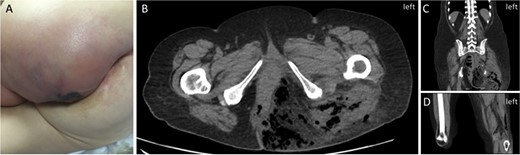

Initial patient presentation. (A) Initial presentation of left buttock on physical exam. (B) CT scan (axial view) demonstrating free air in left buttock. (C) CT scan (coronal view) demonstrating free air in the left thigh. (D) CT scan (coronal view) demonstrating free air extending into left popliteal fossa.

At presentation, this induration had enlarged with a 1-day history of serous discharge and chills (Fig. 2A). All vital signs were normal, but bloodwork revealed leukocytosis of 22 200 and acute kidney injury with a creatinine of 191 μmol/L. Non-contrast CT scan showed performed sigmoid diverticulitis with free air tracking inferiorly into the left pelvis with a 5.5 × 3.3-cm abscess. Significant extension of gas was also seen throughout the entire left buttock tracked posteriorly along the hamstring muscles to the popliteal fossa (Fig. 2B–D). Subcutaneous emphysema rapidly became clinically apparent, and she was taken to the operating room for wide debridement of the left buttock, perineum and leg, with laparotomy, washout and left hemicolectomy (Fig. 3A). Antibiotic treatment with piperacillin/tazobactam, clindamycin and vancomycin was initiated. She was taken back to the operating room the next day for further debridement, drainage of retroperitoneal and pre-rectal abscesses, and end colostomy creation. Final tissue culture revealed polymicrobial gut flora. After 19 days in the intensive care unit, she was transferred to the floor and continued treatment with negative pressure wound therapy for an additional month prior to transfer to a rehabilitation hospital. She returned to the operating room 2 months after initial presentation for delayed wound closure with a rotational flap on the left buttock (Fig. 3B). The left ureteric stent was removed 1 week later, and resolution of hydronephrosis was confirmed on subsequent imaging. Six months after presentation, she developed ulcerating lesions over her left hip. These were biopsied on two separate occasions as the initial suspicion was they represented Marjolin’s ulcers, which are aggressive ulcerating squamous cell carcinomas in areas of previously traumatized, chronically inflamed and scarred tissue and are treated by wide local excision. Instead, they ultimately revealed PG (Fig. 3C), which is not a surgically treated condition. She was consulted to dermatology and initially treated with prednisone, colchicine and azathioprine. Now 2.5 years since presentation, she is chronically maintained with mycophenolic acid and intralesional triamcinolone injections with good effect. Multiple subsequent investigations for immunodeficiency syndromes have been negative.